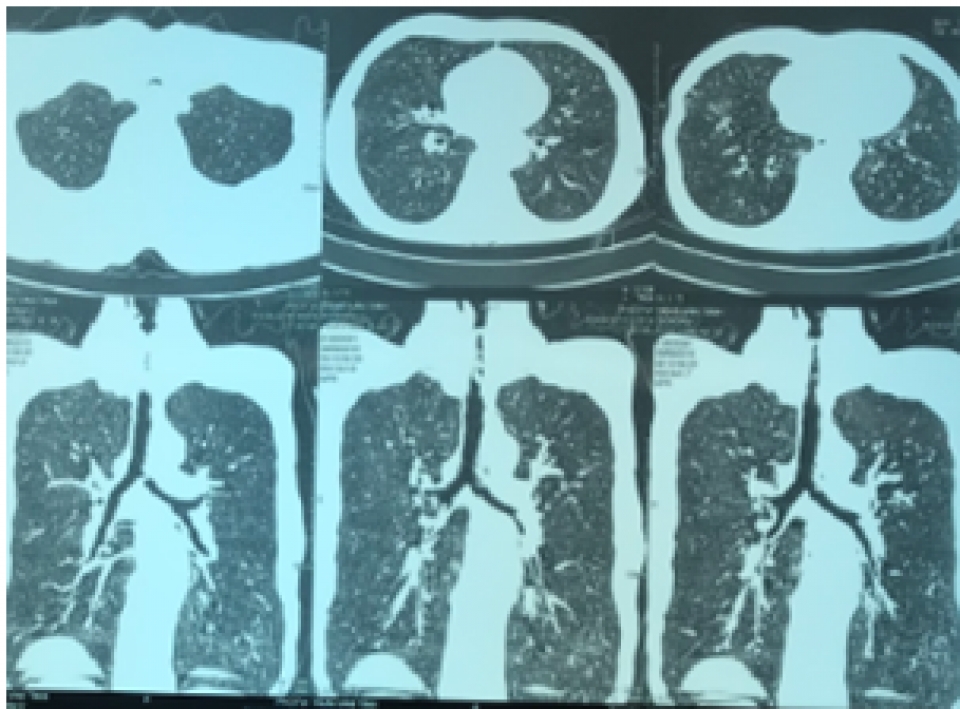

Ngày 24/9, bệnh nhân được chuyển đến Bệnh viện Phổi Trung ương trong tình trạng khó thở nhiều, có tiếng rít thanh quản. Bệnh nhân đã được chụp CT scanner ngực có hình ảnh hẹp khí quản, được nội soi phế quản cấp cứu phát hiện thấy có tình trạng xơ sẹo gây chít hẹp gần hoàn toàn khẩu kính khí quản đoạn 1/3 trên, ngay dưới thanh môn. Tình trạng hẹp khí quản mức độ nặng này có nguy cơ đe dọa tử vong ngay cho người bệnh.

Hình ảnh chụp CT ngực bệnh nhân, có tình trạng hẹp khí quản. (Nguồn: Bệnh viện Phổi Trung ương)